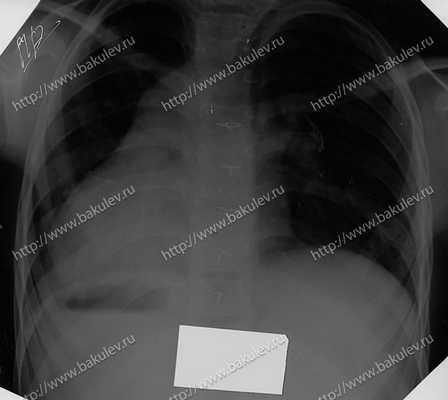

Рентгенограмма органов грудной клетки: ВПС, комбинированный, оперированный, декстракардия. Очаговых и инфильтративных теней не видно. Корни лёгких: левый нечётко структурен, правый не виден из-за тени сердца. Лёгочный рисунок избыточный в нижних отделах с обеих сторон. Сердце расположено в правой половине грудной клетки, расширено, увеличено в поперечнике. Сердечно-лёгочный коэффициент — 67%. Контуры диафрагмы чёткие. Синусы свободные. Г азовый пузырь желудка расположен справа.

Рис 3 — Рентгенограмма органов грудной клетки

Рентгенография органов грудной клетки:

свежих инфильтративных изменений не выявлено. Избыточный лёгочный рисунок — в нижних отделах с обеих сторон. Сердце расположено в правой половине грудной клетки, расширено, увеличено в поперечнике. Декстрокардия. КТИ — 67%.